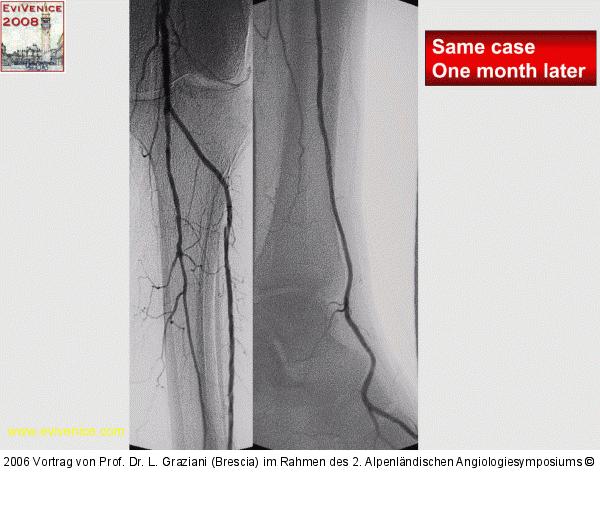

Abbildung 73: Arteria dorsalis pedis - Katheterisation

Arteria dorsalis pedis - Katheterisation